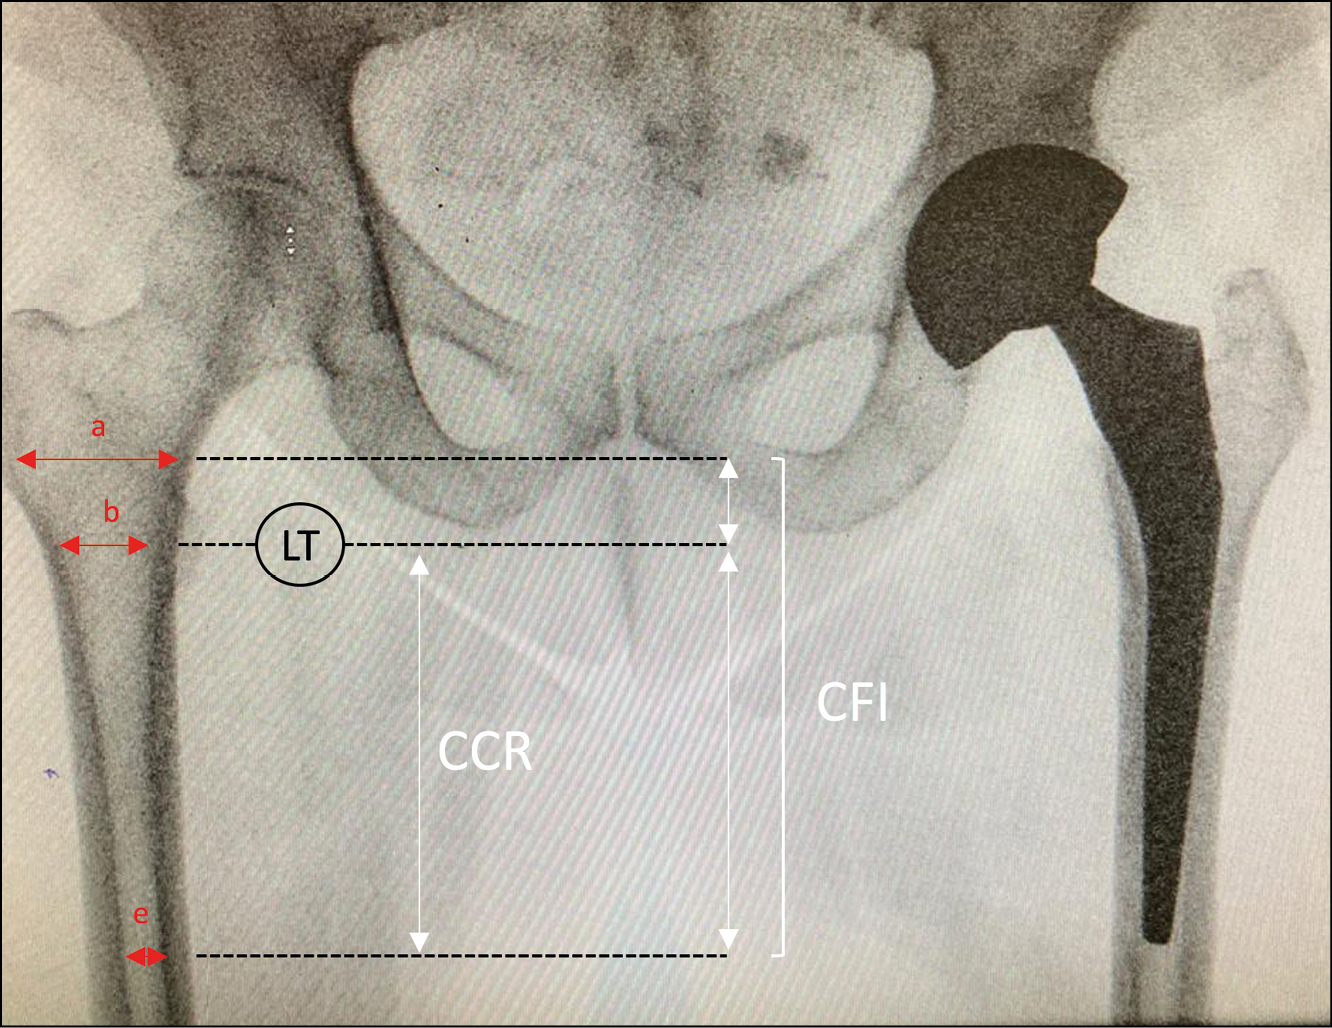

Acetabular and femoral revisions in THA